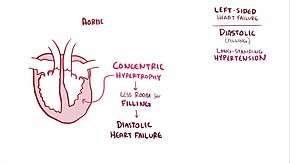

Heart failure is divided into two different types: heart failure due to reduced ejection fraction (also known as heart failure due to left ventricular systolic dysfunction or systolic heart failure) and heart failure with preserved ejection fraction (HFpEF) also known as diastolic heart failure or heart failure with normal ejection fraction.[5][14] Heart failure with reduced ejection fraction occurs when the ejection fraction is less than 40%.[19] In diastolic heart failure, the heart muscle contracts well but the ventricle does not fill with blood well in the relaxation phase.[5] Ejection fraction is the proportion of blood pumped out of the heart during a single contraction.[20] It is given as a percentage with the normal range being between 50 and 75%.[20]

Diastolic dysfunction

Heart failure caused by diastolic dysfunction is generally described as the backward failure of the ventricle to adequately relax and typically denotes a stiffer ventricular wall. The "stiffness" and contractility of the ventricular walls in diastole was first described by Pierre-Simon Laplace. This causes inadequate filling of the ventricle and therefore results in an inadequate stroke volume (SV). SV is a mathematical term amenable to manipulation of many variables. The failure of ventricular relaxation also results in elevated end-diastolic pressures, and the end result is identical to the case of systolic dysfunction (pulmonary edema in left heart failure, peripheral edema in right heart failure).

Diastolic dysfunction can be caused by processes similar to those that cause systolic dysfunction, particularly causes that affect cardiac remodeling.

Diastolic dysfunction may not manifest itself except in physiologic extremes if systolic function is preserved. The patient may be completely asymptomatic at rest. However, they are exquisitely sensitive to increases in heart rate, and sudden bouts of tachycardia (which can be caused simply by physiological responses to exertion, fever, or dehydration, or by pathological tachyarrhythmias such as atrial fibrillation with rapid ventricular response) may result in flash pulmonary edema. Adequate rate control (usually with a pharmacological agent that slows down AV conduction such as a calcium channel blocker or a beta-blocker) is, therefore, of key importance to preventing acute decompensation.

Left ventricular diastolic function can be determined through echocardiography by measurement of various parameters such as the E/A ratio (early-to-atrial left ventricular filling ratio), the E (early left ventricular filling) deceleration time, and the isovolumic relaxation time.